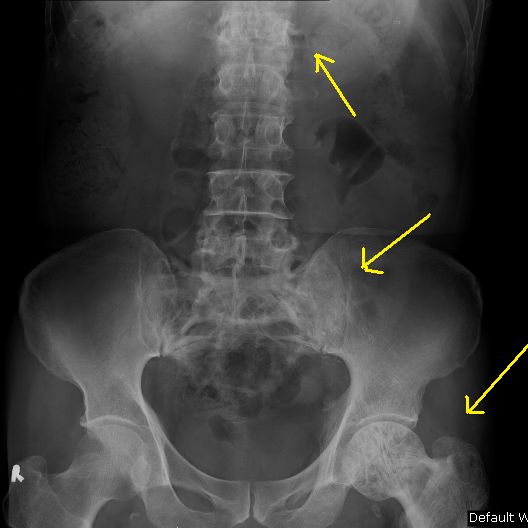

Paget's Disease Of Bone - Sumer's Radiology Blog

disease bone paget pagets radiology murthy dr

Pagets Pictures

pagets paget disease bone hip source 1019 1499